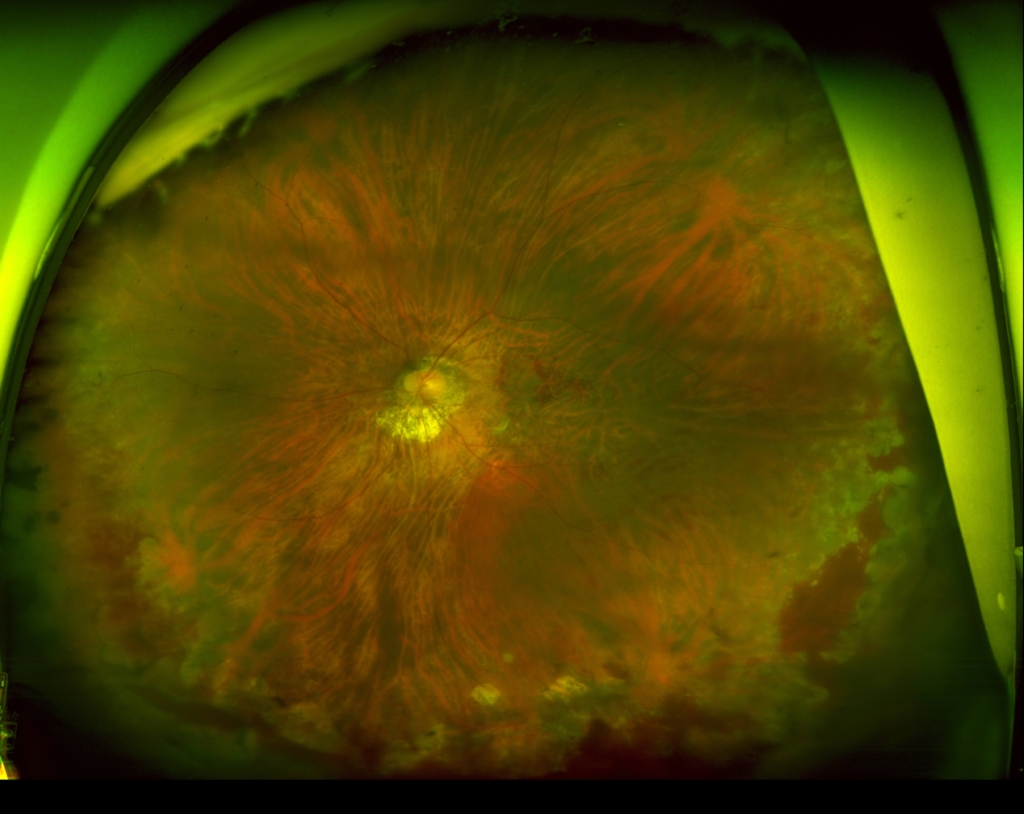

初診時

網膜下出血と出血性PEDがみられる。

低いPEDの内部は中等度~低反射が混在しており新生血管と考えられる。